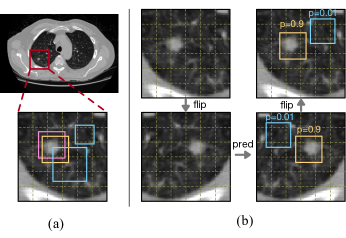

Figure 1: (a) is an example of assigning targets to anchors. The dashed grids represent output feature maps where anchor boxes are defined, and each bin in the grids corresponds to a point in the feature map. The pink box is a ground-truth bounding box. The orange box is a positive anchor and the blue boxes are negative anchors. (b) is an example of our augmentation method used for target prediction. We use flip augmentation for the image patch and predict the probability for each anchor with the model. After that, an inverse transformation is applied to the patch and anchors. We only show two example anchors for illustration purposes and use consistent coloring for each anchor. Note that anchors in 3D images are also three-dimensional, of which we only show 2D slices for better visualization.

Following the common practice in computer vision, we sample patches of the same size (160×160×160160160160160\times 160\times 160 in our experiments) from original images during training. We also ensure that the edge length of image patches (e.g., 160) is divisible by the maximum strides (e.g., 16) used in FPN. Consequently, each anchor in an image patch can always fall into the position of another anchor after rotating or flipping. We define the augmentation for each patch as applying these two types of transformations on it. It is worthwhile mentioning that there are richer combinations of rotation and flipping in different directions for 3D medical images than those in the 2D case (48 different combinations versus eight). Then, we use the model to predict the probability of each anchor matching an object in the transformed image patch. After that, we can obtain a guessed target for each anchor in the original patch by an inverse transformation (rotating or flipping backward). The reader can find an intuitive example in Figure 1.